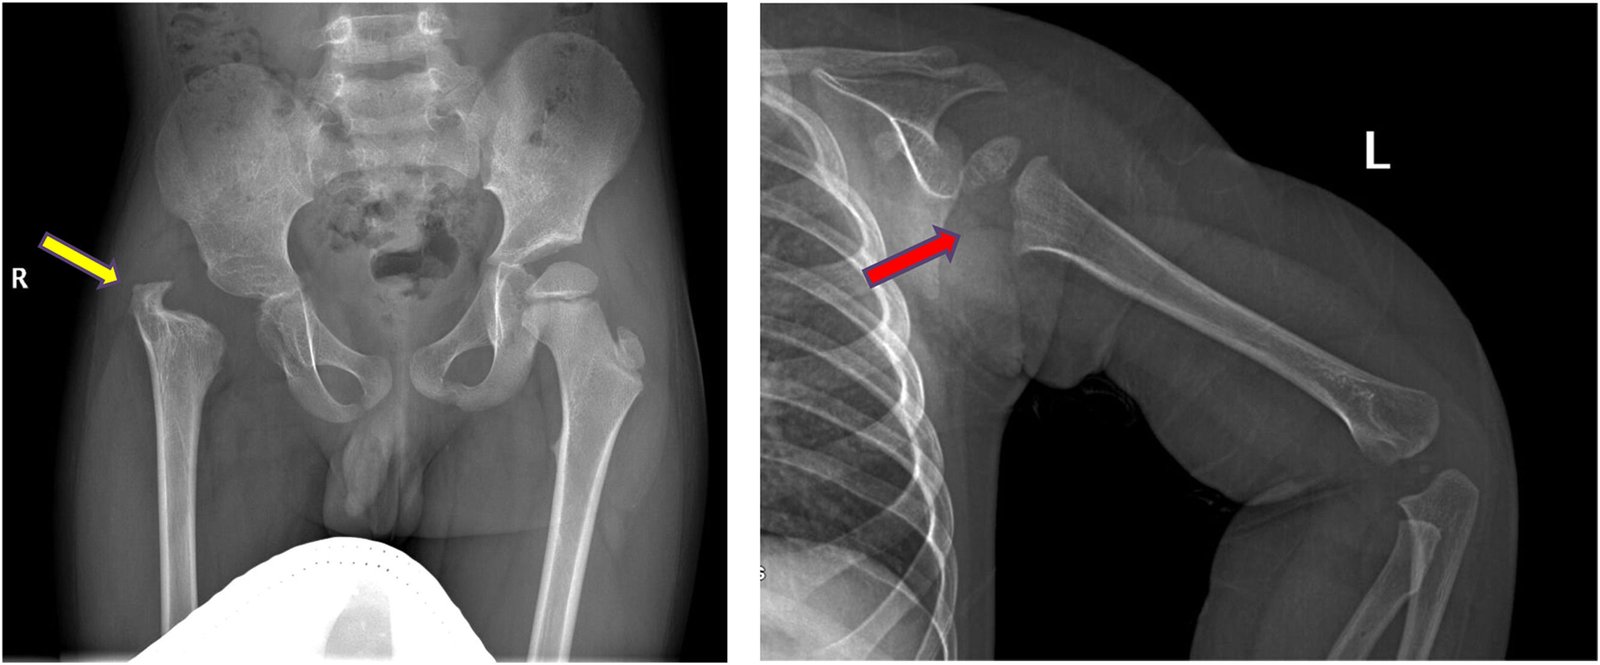

Bone Infections (Osteomyelitis) & Joint Infection (Septic Arthritis)

Infection in bone or joint is a serious condition. If not detected and treated early, it can lead to grave consequences and pose risk of morbidity and mortality to the patient.

Treatment of bone and joint infection , whether primary or secondary due to some orthopaedic surgery where there is presence of implant or after joint replacement, is available at our hospital. Various modalities used to treat infection include radical debridgement, antibiotic loaded beads, antibiotic coated implants, Illizarov fixator to address bone defect and to correct limb length.